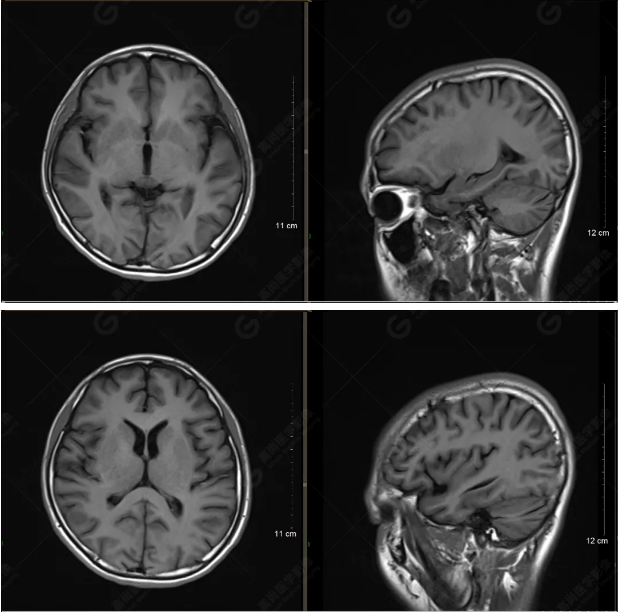

以下是T1WI軸位掃描及矢狀位掃描:

雙側(cè)大腦半球?qū)ΨQ,灰白質(zhì)對比正常,顱內(nèi)未見異常信號影。腦室系統(tǒng)未見擴(kuò)大,中線結(jié)構(gòu)居中。腦溝、裂未見增寬。幕下小腦、腦干未見異常。矢狀位示垂體形態(tài)、大小級信號未見異常。所示左側(cè)乳突內(nèi)見多發(fā)短T1長T2信號影。

顱腦MRI平掃未見明顯異常,左側(cè)乳突內(nèi)積血,建議補(bǔ)充SWI檢查。